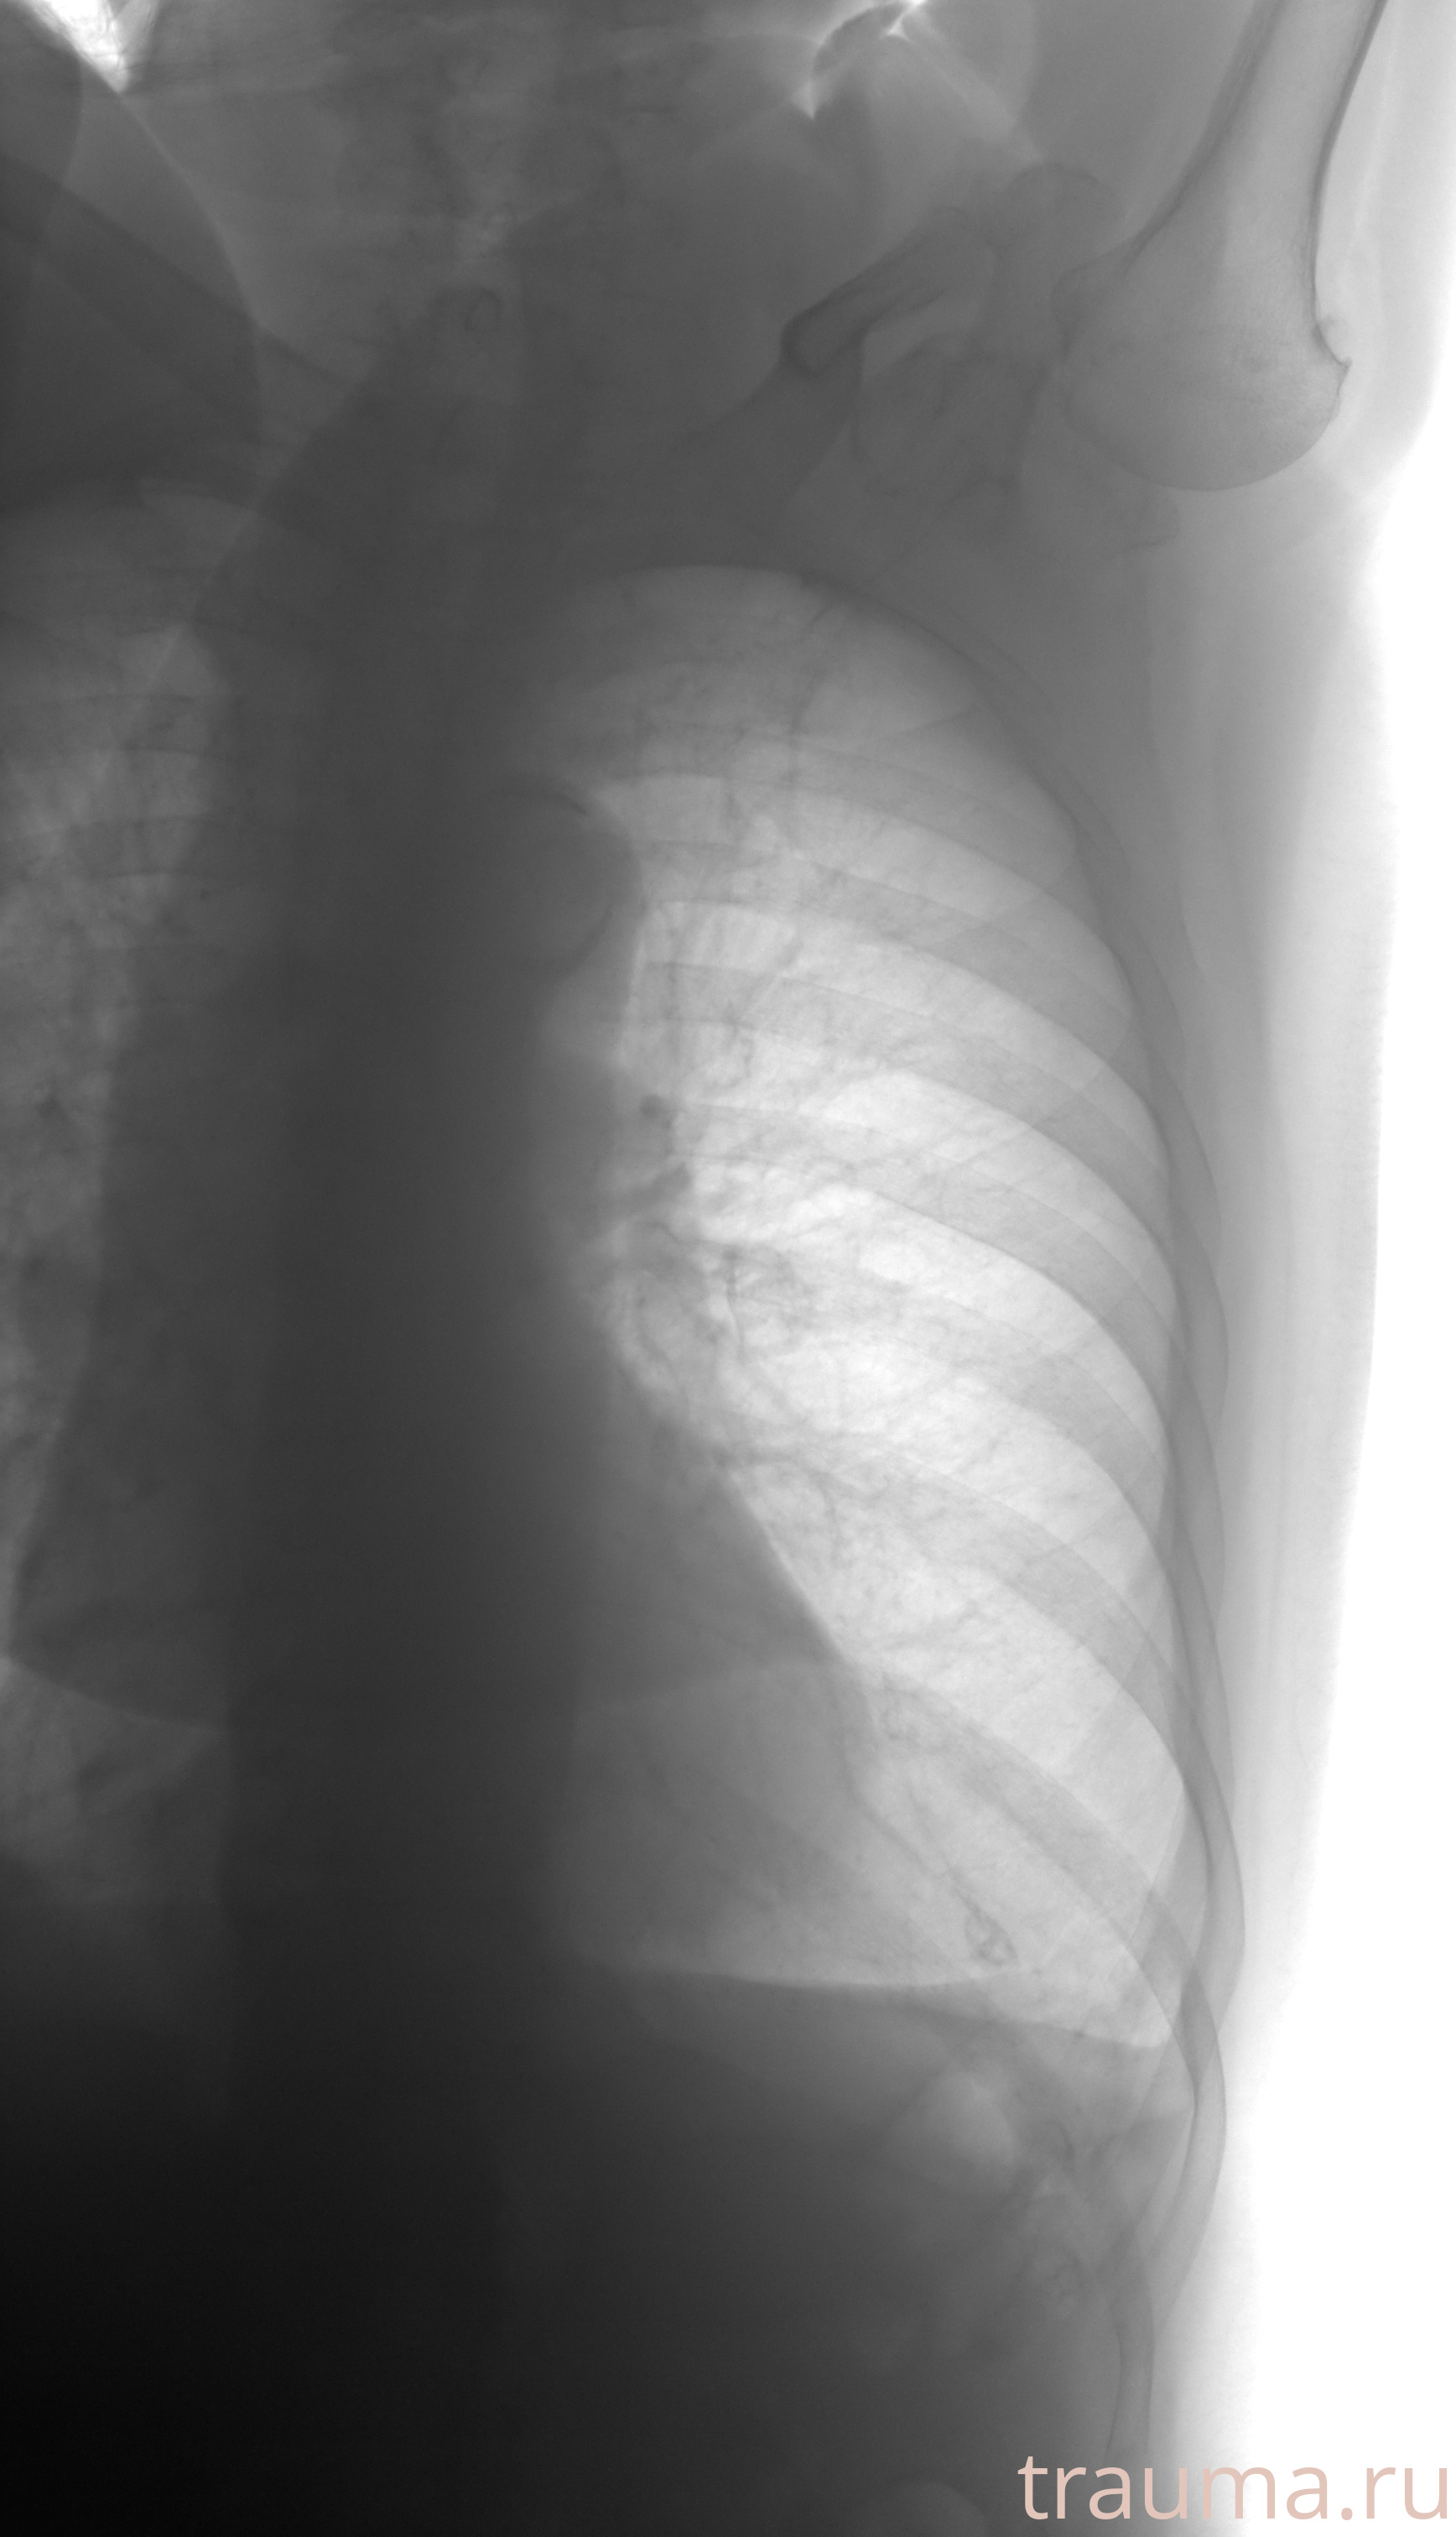

Рентгенограммы

Рентген на дому: по вашему адресу приезжает врач-рентгенолог, травматолог-ортопед с мобильным рентгеновским аппаратом, проводит диагностику травмы или заболевания, делает необходимые рентгенограммы, дает рекомендации по дальнейшему лечению. Получить качественные снимки в домашних условиях возможно благодаря уникальной методике, разработанной МосРентген Центром для института  Склифосовского

при переломе шейки бедра и пневмонии от компании МосРентген Центр - партнера Института имени Склифосовского